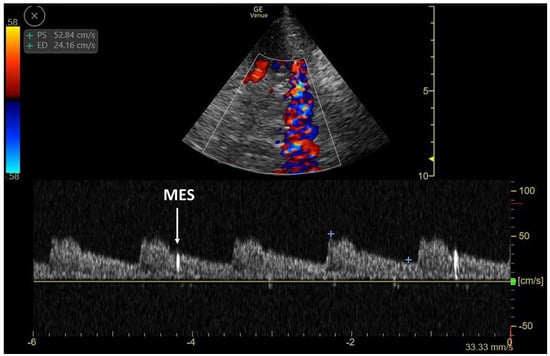

3.1. TCCD MES-Positive Case 1

3.2. TCCD MES-Positive Case 2

3.3. TCCD MES-Positive Case 3